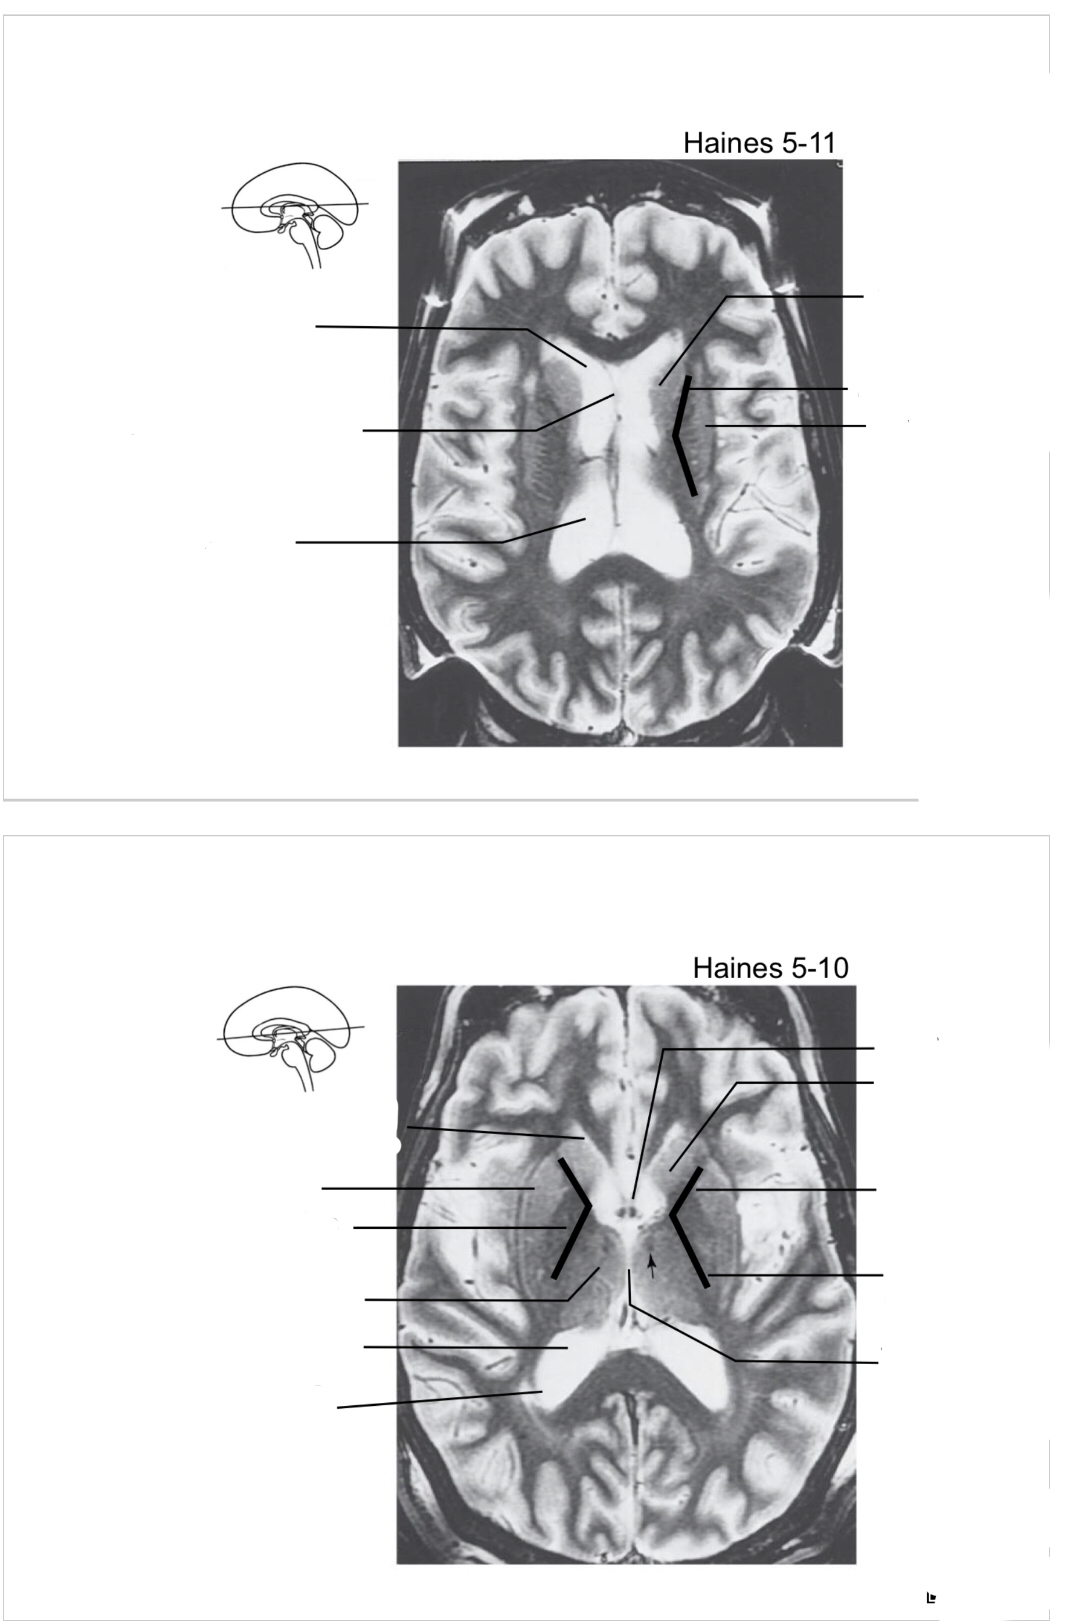

The structure indicated by the red line is? BONUS: SYMPTOMS IF THERE IS A LESION

motor spatial and directed movements (role in parkinsons?)

Bonus: Split Brain. L and R can’t communicate. Remember the test he did in class where he made us wave? Diagnose like that b/c wernickes is on left side so you cant wave ur left